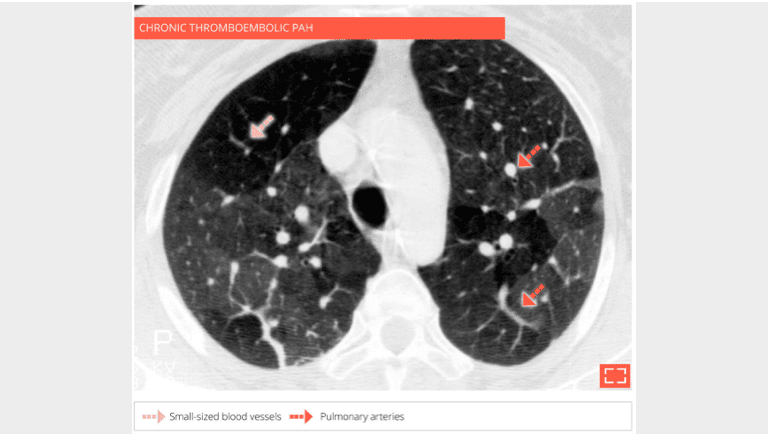

The hypodense regions of the lung contain smaller vessels, the number of which decrease while the size of the pulmonary arteries in dense regions increases corresponding to a redistribution of vascular flow to these perfused regions. A CT scan with injection of contrast agent synchronized to opacification of the pulmonary arteries, must confirm chronic thrombosis of the pulmonary arteries.

2. Vascular mosaic attenuation

The CT scan with contrast medium injection to check for pulmonary artery obstruction shows the small size and distal thrombosis of peripheral pulmonary arteries, confirming chronic thrombosis. Ventilation-perfusion scintigraphy is the recommended exam for screening for these anomalies.